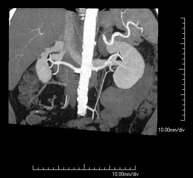

- Abdominal aorta CT angiography

A non-invasive diagnostic test that involves studying the abdominal aorta by obtaining high-definition anatomical images using CT (computed tomography) equipment and iodinated contrast. With the aid of workstations specialised for arterial studies, the image quality supports 2D and 3D reconstructions. It is indicated in patients with vascular disease (atherosclerosis), aortic aneurysms, abdominal pain of possible vascular origin, pre-surgical studies of lesions adjacent to the abdominal aorta as a vascular ‘map’, etc. Information obtained non-invasively is indispensable for patients requiring percutaneous or surgical processing. In patients who only require tracking of vascular lesions, this technique is the non-invasive technique of choice, together with MRI angiography.